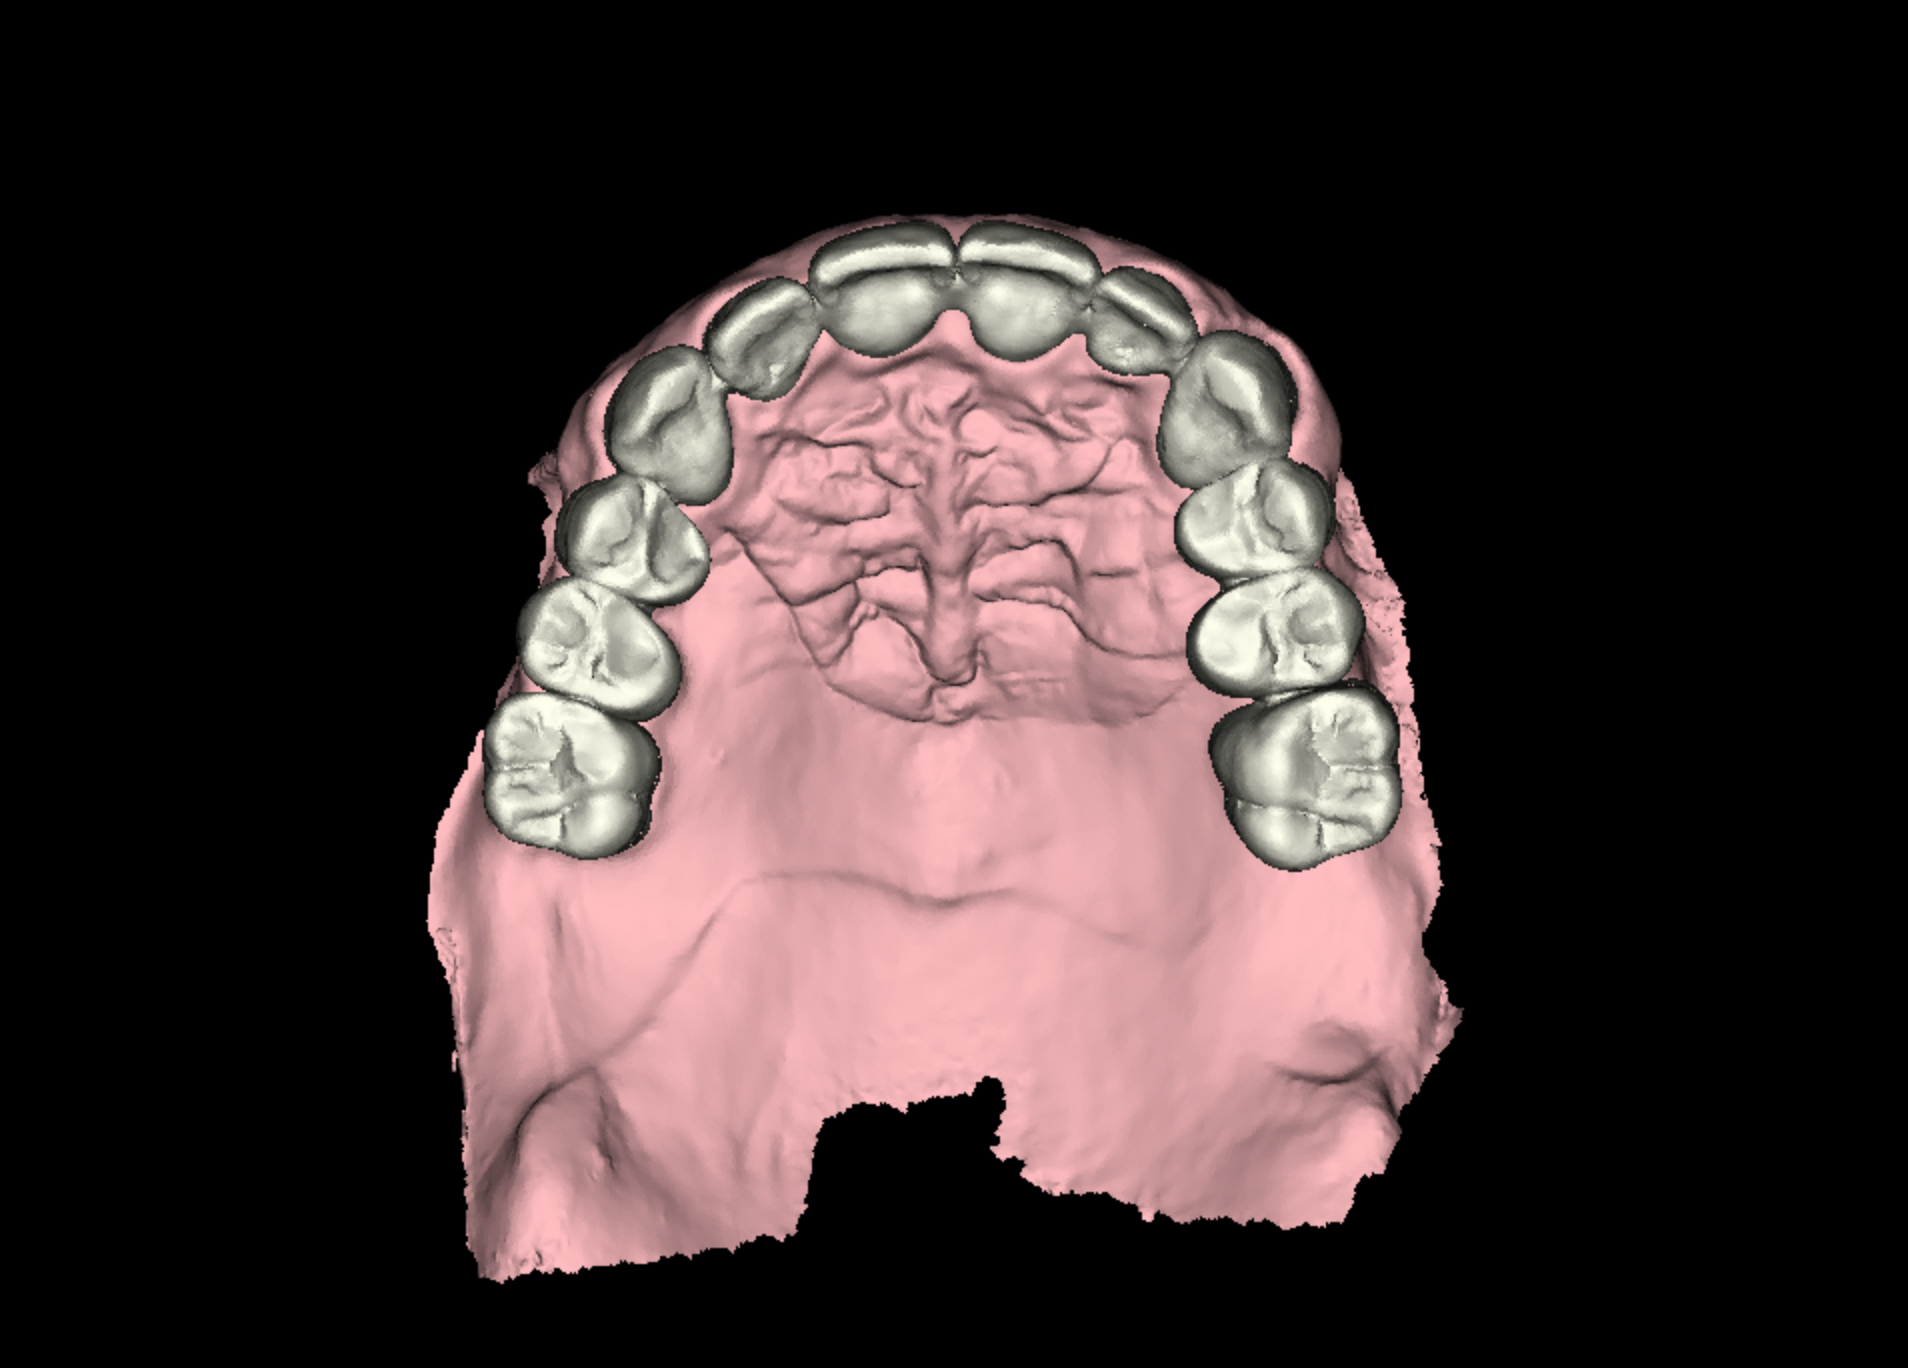

Digital Diagnostics and Virtual Planning

Initial diagnostics included CBCT imaging and full-arch intraoral scanning. A digital wax-up with an increased vertical dimension of approximately 2 mm was created to simulate functional and aesthetic improvements. Fully digital implant planning was carried out, and a SMOP tooth supported guide was designed, anchored in the region of the lateral incisors.